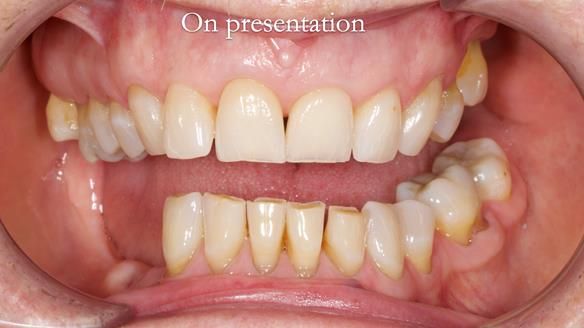

Joyce's Case Presentation 61

Welcome to Newsletter 61. In this edition, I walk through the process of creating and fitting a metal based lower partial denture for Joyce, a fit and healthy 76 -year-old woman.

Joyce self-referred to me for specialist prosthodontics.

The missing lower right teeth to be replaced with a metal based partial denture.

The detailed clinical situation and treatment process are outlined below, with clinical work provided by me and technical work by Rowan Garstang. The treatment spanned six visits for denture fitting and one review.